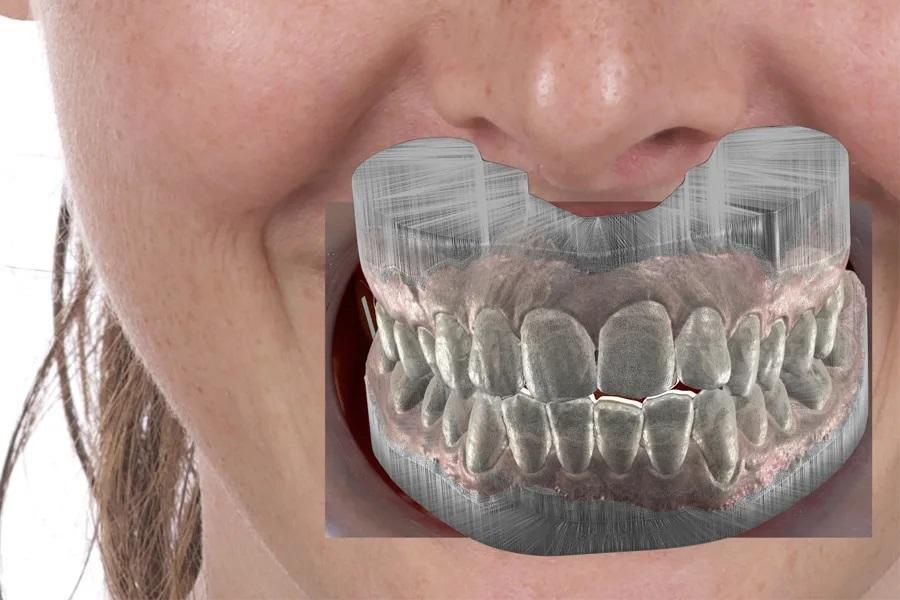

Цифровое моделирование улыбки (в универсальном программном обеспечении) используется для согласования лицевых параметров с положением зубов, коммуникации в команде и формирования поэтапного плана ортодонтического лечения и целей интрузии. Это также позволяет визуализировать различия между стратегиями «закрытия спереди» и интрузии боковых зубов у пациентов с высокой экспозицией зубов. (фото 6 – 8)

Фото 8. Переход от 2D (как на фото 8) к 3D — от дизайна улыбки к поэтапному планированию элайнеров.